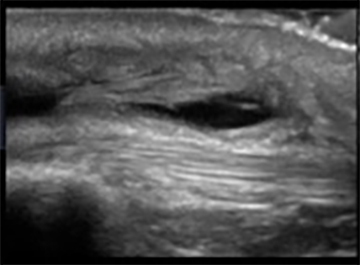

Knee Infrapatellar Pre-Patellar Bursitis Image